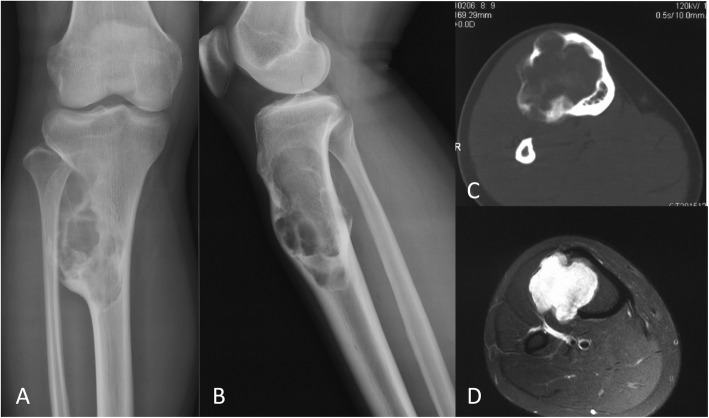

OFD-like and classic AD showed similar imaging characteristics (Figs. 1 and 2). The tumor was located in the cortex of the tibia or fibula, which showed expansile lytic lesions with varying degrees of osteolysis and osteosclerosis. CT showed cortical destruction, with cysts separated by sclerotic bony septa. MRI revealed different tumor foci with high signal intensities on T2-weighted images and T1-weighted contrast-enhanced images. Imaging showed whether the lesions were fibro-osseous, but neither CT nor MRI was able to differentiate between OFD-like and classic AD.

Fig. 1.

Representative images of osteofibrous dysplasia-like adamantinoma. Radiographs showing a anterior-posterior and b lateral views of the tumor in the tibial shaft. c CT image showing the extent of the tumor in the cortex. d MRI showing the extent of the tumor